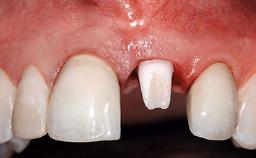

A 36-year-old male patient with a compromised maxillary central incisor was referred by his general dentist for consultation. The patient’s chief complaints were the gradual debonding of a temporary crown on the right central incisor and unsatisfactory esthetics due to an increasing diastema between the right central and lateral incisors. The patient reported a traumatic event some years previously, when a crown had been placed after root-canal treatment. The referring dentist wanted to provide a new crown restoration, but was concerned about the condition of the residual root. Anamnesis was negative for any other dental or periodontal pathology in the remaining dentition. The patient reported taking no medications: He was a smoker (10 to 15 cigs/day) and had realistic esthetic expectations.